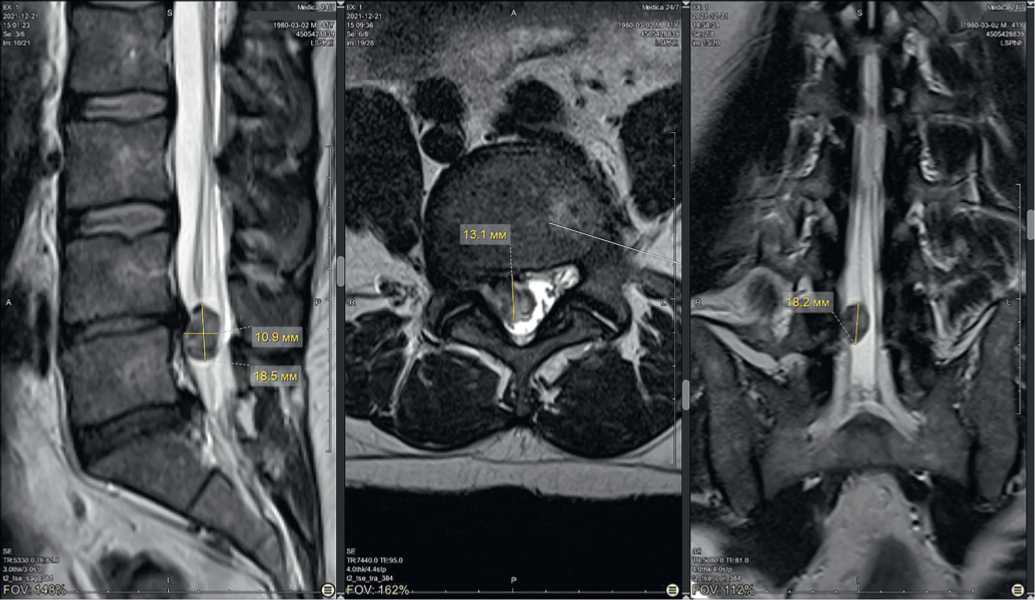

Клинические пример 1

Пациент К., 41 года, обратился в Центр китайской медицины «Синь-я-Чжу» 22.12.2021 с жалобами на постоянную острую боль в пояснице с иррадиацией в правую нижнюю конечность, онемение пальцев стопы; движения ограничены — не может наклоняться, трудно сидеть. Ранее обращался к остеопатам и массажистам — без эффекта. Данные магнитно-резонансной томографии (МРТ) — грыжи дисков L4–L5, выступающая в спиномозговой канал на 13 мм, ширина секвестра 14 мм, каудальное распространение на 18 мм (рис. 2). Консультация нейрохирурга — рекомендовано оперативное лечение.

Рис. 2. Исходная магнитно-резонансная томограмма пациента К. при обращении 22.12.2021: A) саггитальный срез, B) аксиальный срез на уровне межпозвонкового диска L4-L5, C) фронтальный срез

Fig. 2. Initial magnetic resonance imaging of patient K. upon presentation on 22.12.2021: A) sagittal section, B) axial section at the level of the intervertebral disc L4-L5, C) frontal section

После лечения акупунктурой в течение 2 месяцев при контрольной МРТ от 07.03.2022 отмечена положительная динамика: уменьшение глубины грыжевого выпячивания до 7,5 мм, каудального распространения до 9,2 мм (рис. 3).

Рис. 3. Магнитно-резонансная томограмма пациента К. на фоне лечения 07.03.2022: A) саггитальный срез, B) аксиальный срез на уровне межпозвонкового диска L4-L5, C) фронтальный срез

Fig. 3. Magnetic resonance imaging of patient K. during treatment on 07.03.2022: A) sagittal section, B) axial section at the level of the intervertebral disc L4-L5, C) frontal section